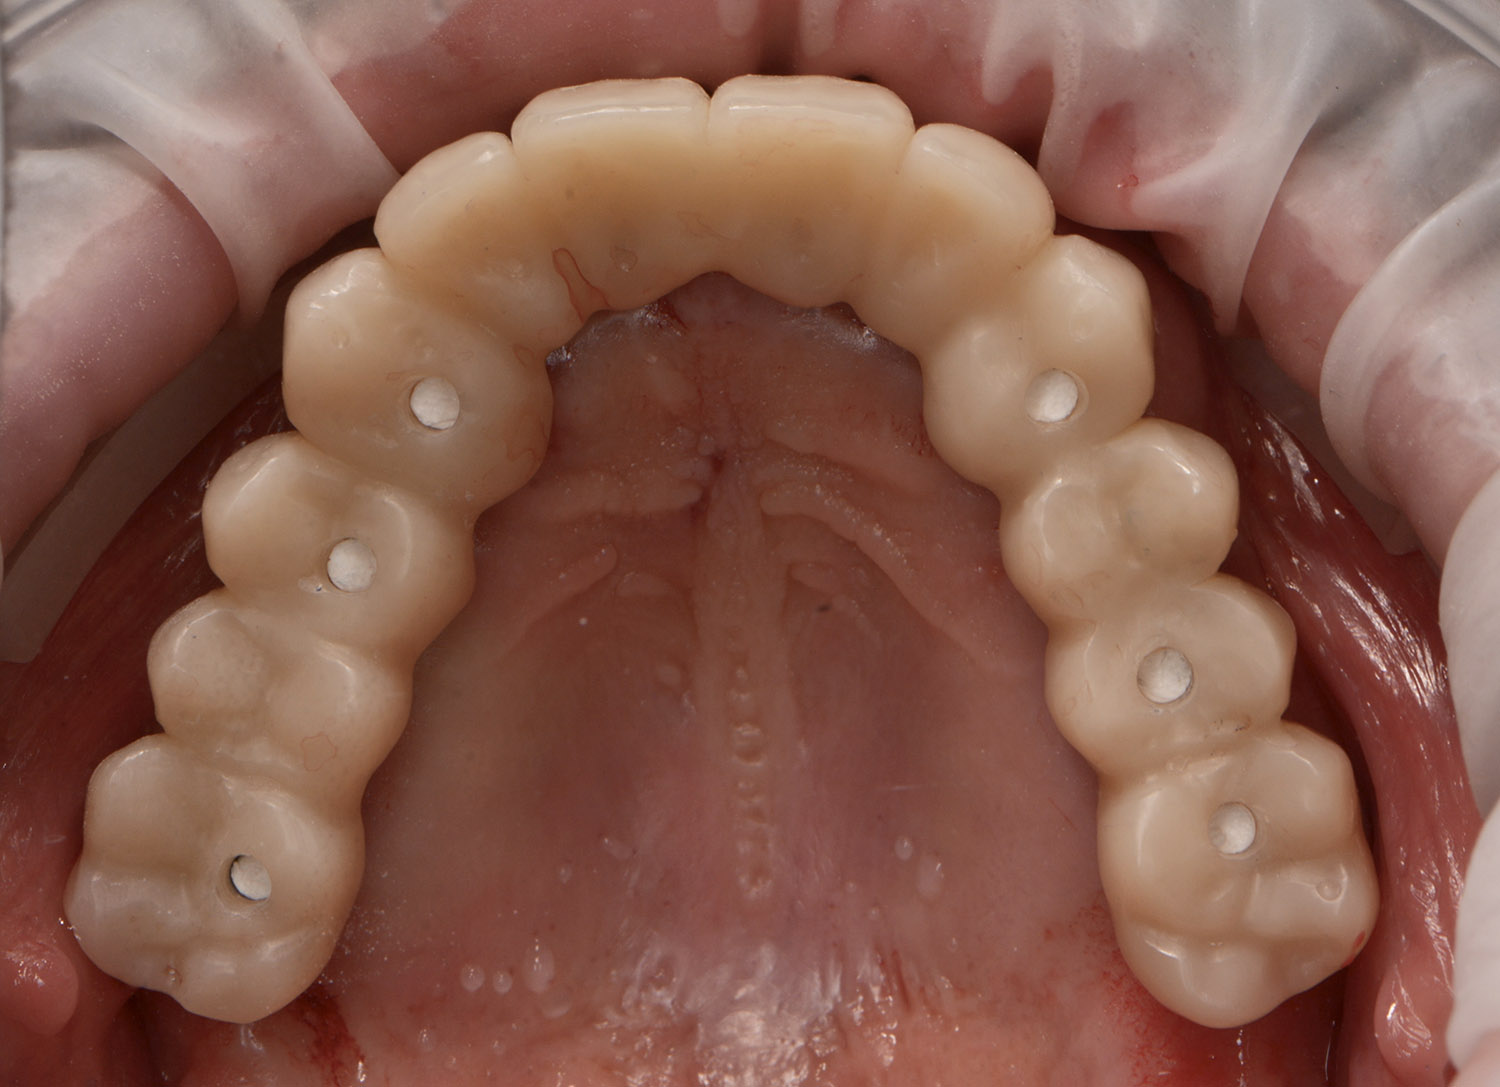

Una volta inserito l’impianto, prende avvio un processo di guarigione che porta alla sua integrazione nell’osso (osteointegrazione). In base alle indicazioni e al quadro clinico è possibile inserire uno o più impianti creando, quindi, le premesse per l’applicazione di una corona singola o di un manufatto protesico, più o meno esteso.

Gli impianti possono anche rappresentare un’ottima strategia di trattamento nei soggetti totalmente edentuli.